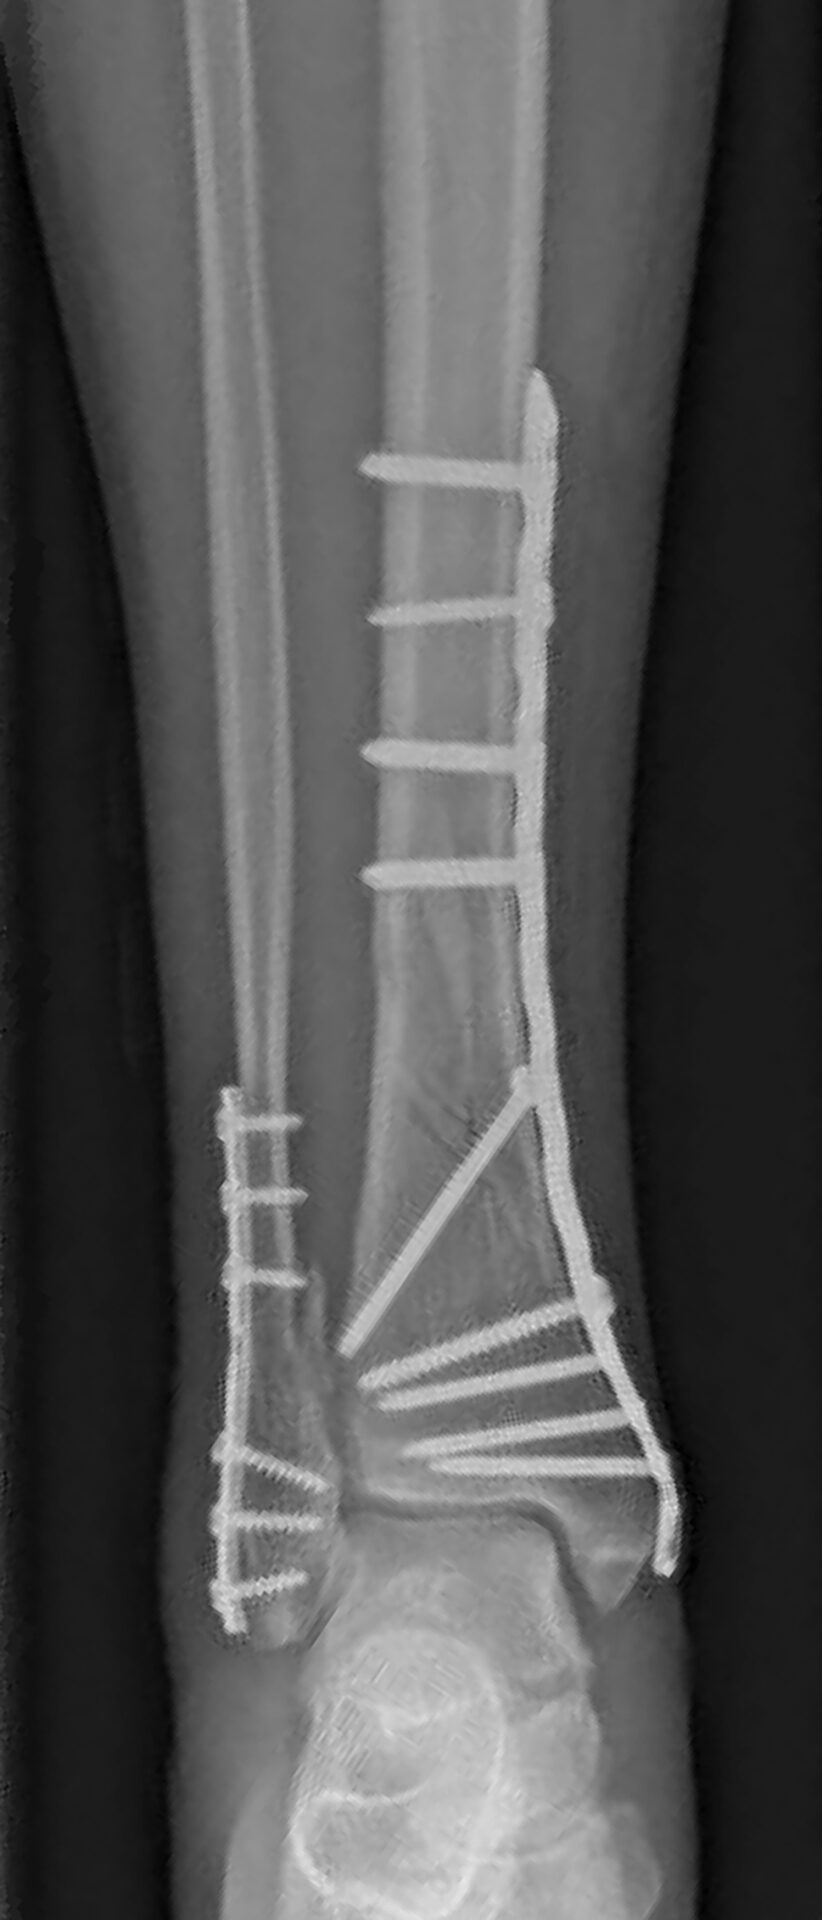

Figuur 5.

Verschillende operatieve opties voor de behandeling van fracturen van het onderbeen met: A. platen en schroeven; B. pen die geplaatst is in de mergholte van het scheenbeen.